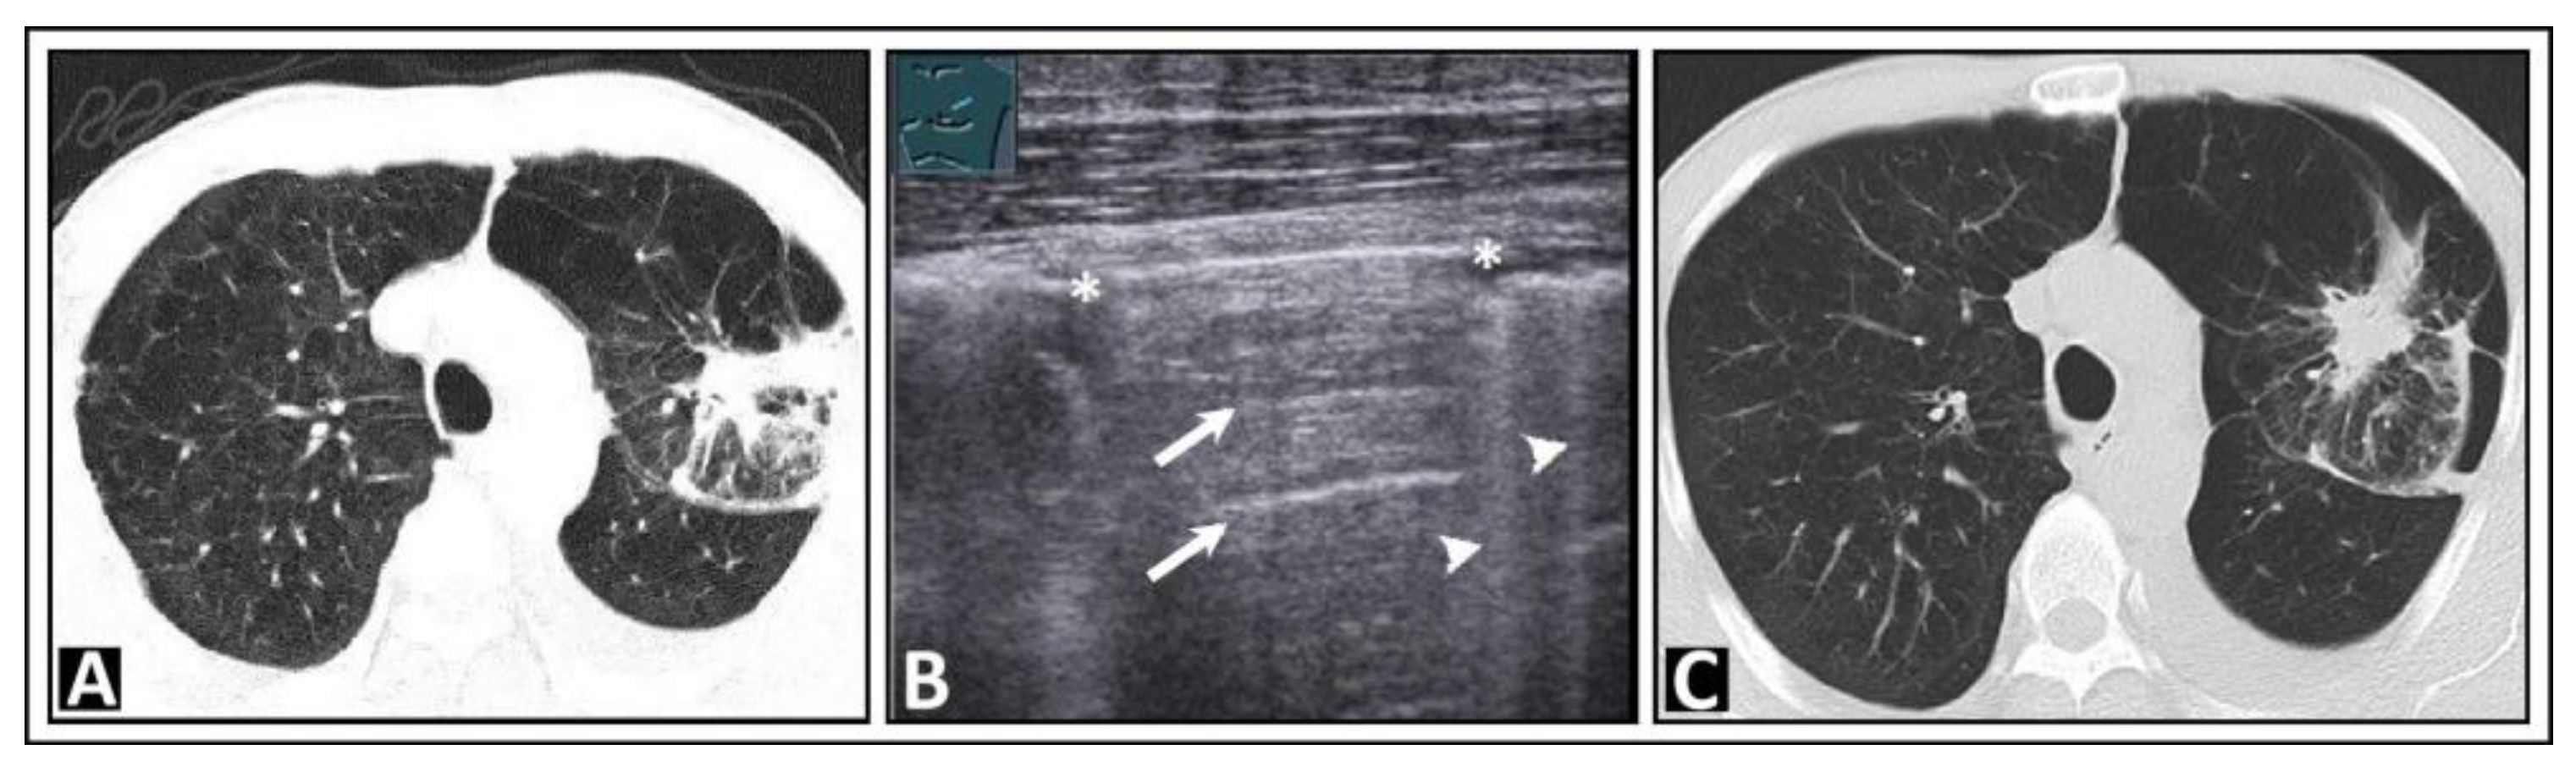

4. Pulmonary Edema and Acute Respiratory Distress Syndrome

5. Pneumonia

6. Interstitial Lung Disease